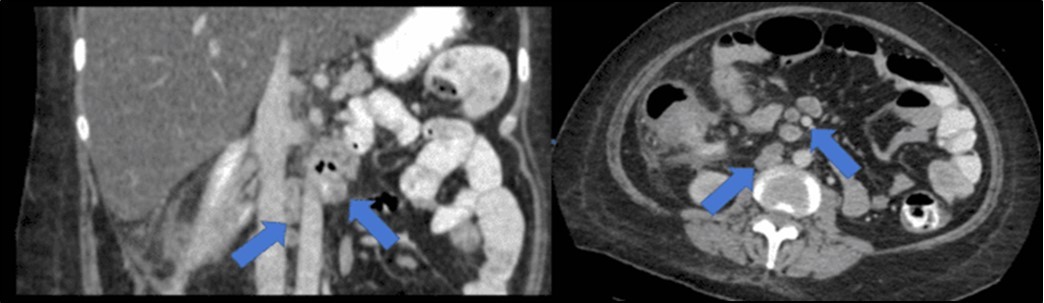

There was no evidence of malignancy or IBD seen during both endoscopic procedures. Computed tomography (CT) scan of the whole abdomen was done which showed inflammatory changes involving the cecum and adjacent duodenum and ileum with coloenteric fistulae. There was noted progression of abdominal lymphadenopathies as well as ascites. Main consideration was an infectious disease process (i.e. TB) (Figure 2, Figure 3, Figure 4 to Figure 5).

Figure 5.Enlarged and necrotic abdominal nodes in the mesenteric, pericecal, pericolic, para-aortic, paracaval and inter-aortocaval regions. Prominent and enlarged nodes also located in the common hepatic and periportal regions